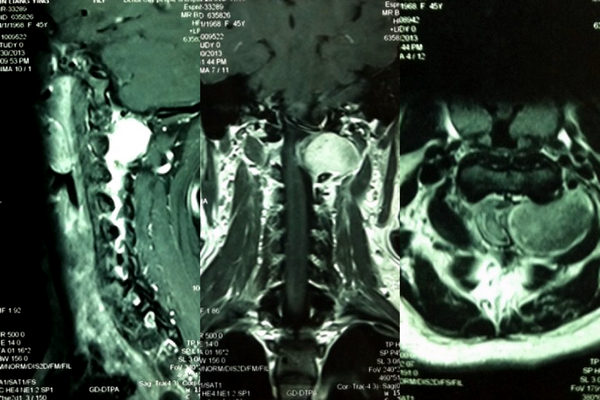

术前MRI检查发现椎管内外肿瘤

病理报告显示神经鞘瘤(左图),术后复查MRI显示完全切除(右下图),术中切除的肿瘤大体形状(右上)